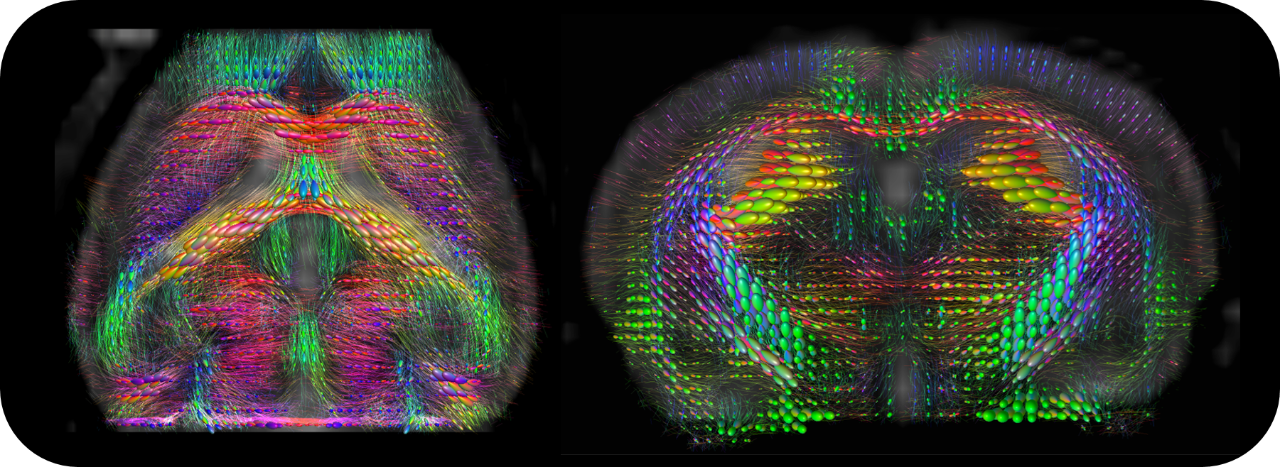

• Intuitive software package, for multi-dimensional MRI/MRS data acquisition, visualization, reconstruction, and analysis of MRI and/or PET/MR data

• MRI sequence portfolio of more than 1,000 sequence variations, including wireless cardiac imaging using navigator based IntraGate methods with cartesian or radial readout, as well as short echo time imaging, such as UTE and ZTE